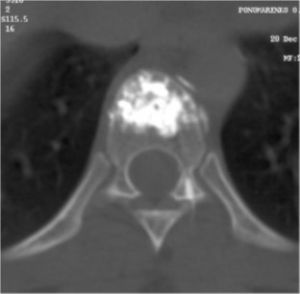

Рис. №6. КТ Th7 позвонка. Заполнение всего тела позвонка костным цементом.

МРТ7